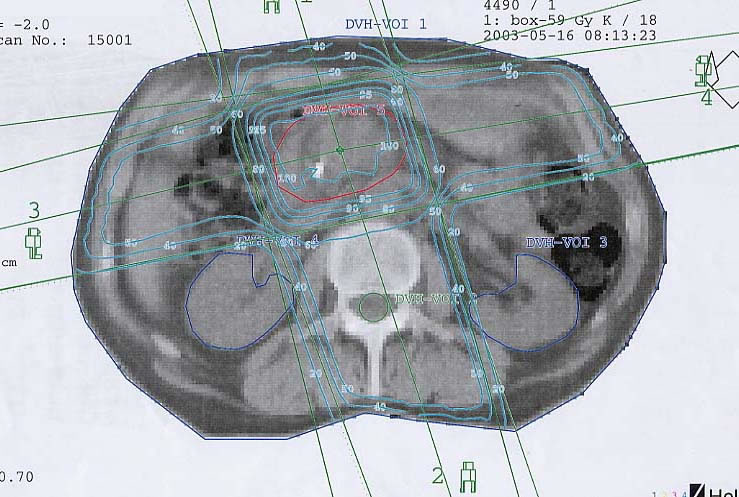

Tumore der Bauchspeicheldrüse (Pankreas): Bestrahlungsplan

Bestrahlungspläne